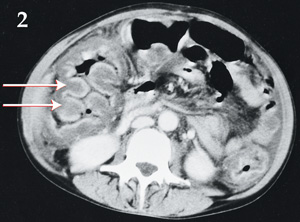

A 39-year-old woman with AIDS (CD4 count, 30 cells/mL) had a 4-day history of nausea, vomiting and profuse watery diarrhoea. The patient was afebrile and had a distended abdomen with diffuse guarding without rebound tenderness. Abdominal x-rays (Box 1) and computed tomography scans (Box 2) were performed. The white blood cell count was within normal limits and stool cultures were negative. Colonoscopy revealed yellow plaques throughout the colon. The patient improved clinically after taking oral metronidazole.

Bowel wall "thumbprinting" (the appearance of "thumbprint"-shaped projections) is a radiological sign of thickening of the colonic wall. It occurs secondary to submucosal haemorrhage and oedema from capillary leakage.1 It can result from any process that leads to oedema of the bowel wall, including pseudomembranous colitis (as shown here), ischaemic colitis, non-infective inflammatory bowel disease, other infective bowel diseases, submucosal/intramural haemorrhage and other conditions.2 The mucosal damage and inflammation seen in pseudomembranous colitis are caused by Clostridium difficile toxin.3